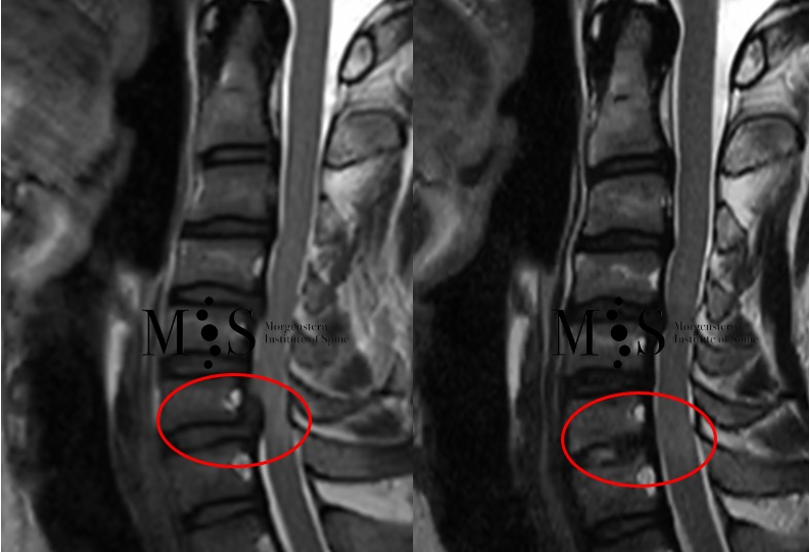

Imatge esquerra: Imatge d’RMN d'una compressió de la medul·la cervical als nivells C6/C7 (marcada amb el cercle vermell) amb signes de mielopatia. Imatge dreta: imatge de control d’RMN del mateix pacient 2 mesos després de la cirurgia en la qual s'observa la descompressió completa i l’alliberament de la medul·la espinal.

Pacient de 48 anys amb una compressió de la medul·la espinal cervical als nivells C6/C7 i mielopatia del cordó medul·lar en aquest nivell. Se li va realitzar descompressió per cirurgia endoscòpica anterior per una incisió de 9 mm de longitud. Al cap de poques hores de la cirurgia el pacient es movia lliurement i rebia l’alta hospitalària poques hores després.